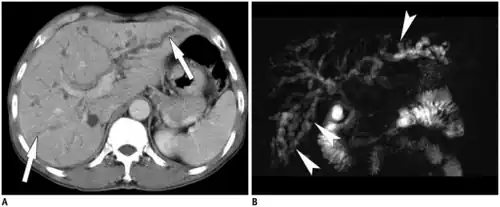

Typical imaging features center around imaging of the liver with CT, ultrasound, or MRI for detection of primary biliary cirrhosis. Traits that raise suspicion for the infection include intra- and extrahepatic dilatation and structures with intraductal pigmented stones, usually in the absence of gallstones and with regions of segmental liver atrophy, particularly the lateral aspect of the left hepatic lobe. Also, reduced arborization of peripheral ducts is seen. A full 5% of chronic infections go on to develop cholangiocarcinoma.[28]